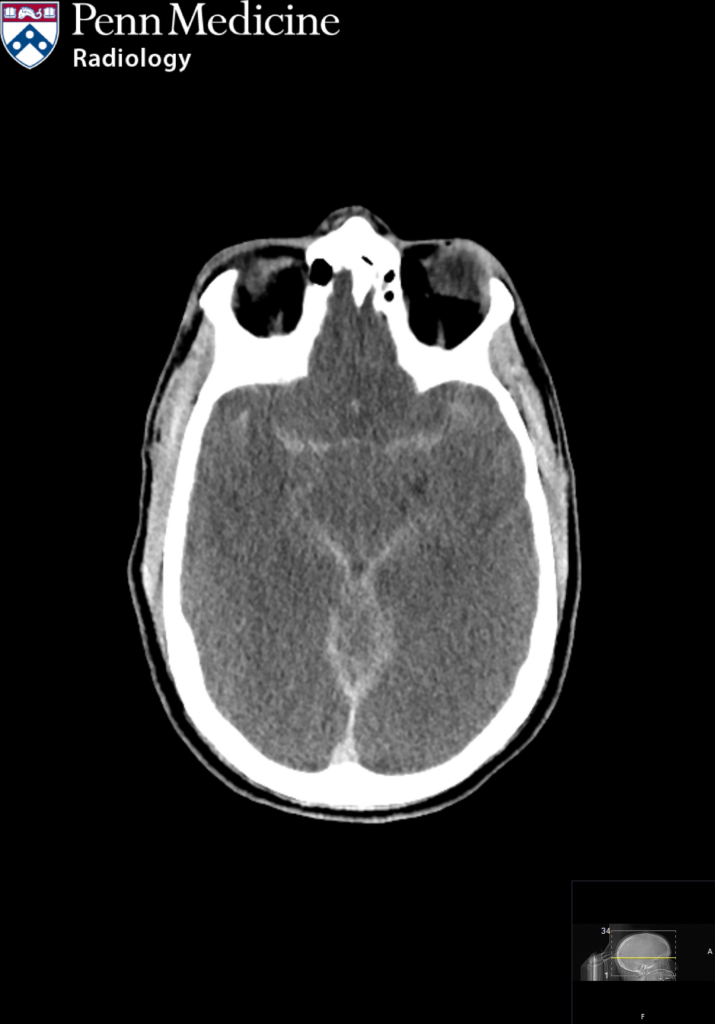

64-year-old man found down

A 64-year-old unresponsive man found down at home.